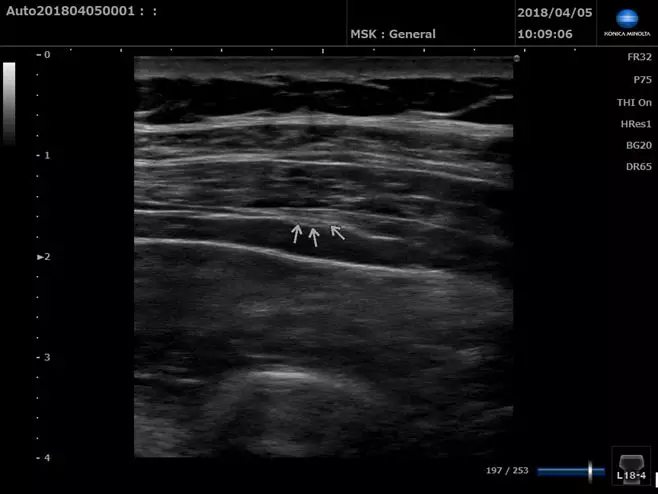

超聲下的姆長屈肌腱(長軸)

■ 上圖為患側,下圖為健側,患側肌腱增粗,A1滑車低回聲增厚(白色箭頭處)